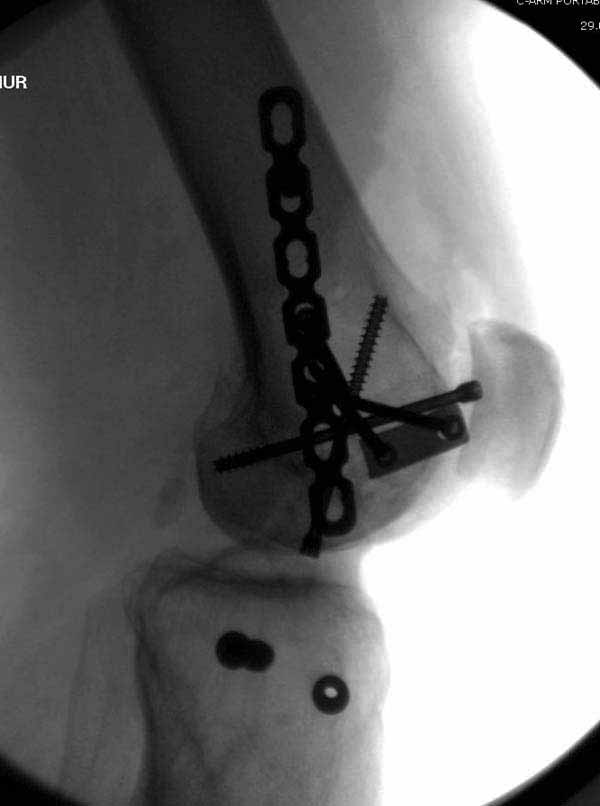

У больных как в этом случае, с вовлечением двух мыщелков правильно, что сделали вытяжение до операции. Здесь имеется флексионный компонент на другой стороне, и я бы рекомендовал операцию делать из двух доступов. Сперва фиксировать медиальную колонну custom made пластиной, обычно 1/3 тубулярной пластиной в 4.5 мм, потому что пока производители опаздывают с медиальной пластиной.

Пластину надо устанавливать на апексе перелома, иначе фрагмент начнет сползать. А на второй стороне, если имеется большой одиночный фрагмент тогда проблем не бывает, и их можно собрать компрессирующими винтами. Проблема наступает тогда когда многофрагментраность на латеральной стороне, где надо применить комбинированный метод, иногда несколькими пластинами. Или сменой позиции установки пластины, чтобы максимально прикрыть перелом и создать боковую поддержку.

Случаи могут быть разными и варианты фиксации могут быть различными. Это не эталон фиксации, и не каждый метод является "золотым стандартом". А “золотым” считается, когда внутрисуставной перелом отрепонирован на отлично и зафиксирован адекватно. Если возможно закрыто - хорошо, а так не надо искать только легкий закрытый путь, зная анатомию можно открывать, сколько надо!

Здесь пример медиальной пластины и латеральный комбинированный метод (у второго больного старый перелом тибиал плато, леченный где то и когда то)

В приложении пример недавней операции, C3, открытая репозиция, фиксация мыщелков спицами и винтами, ретроградный синтез большеберцовым гвоздем 10,5 мм диаметром, винты 5 мм.

Коллеги, извиняюсь за задержку с результатом. Через медиальную артротомию обнажили н/3 бедра, отрепонировали внутренний мыщелок, затем по нему сопоставили суставную поверхность бедра с латеральным мыщелком.

Больная выписана в ортезе с регулируемым углом сгибания в колене, с рекомендациями через 3 нед. удалить спицы и начать разрабатывать сустав.

По прямому снимку репозиция удалось, поздравляю! А с латеральной стороны подозрение на флексионный компонент латерального мыщелка остается, а снимок получился косым, надо было бы повторить.

Выбор имплантов не совсем удачный, подкожно выступающие болты в мыщелках вскоре могут привести к проблемам. Вместо солитарной фиксации болтом-стяжкой дистально можно было бы добавить пару винтов, которые создали бы ротационную стабильность и межфрагментарную компрессию.

Возможно, есть скрытый замысел, неочевидный для нас - не понятны латерально оставленные спицы. Спицы возможный очаг вторичного осложнения, и, тем более у взрослых, тонкие спицы не создают адекватную фиксацию.